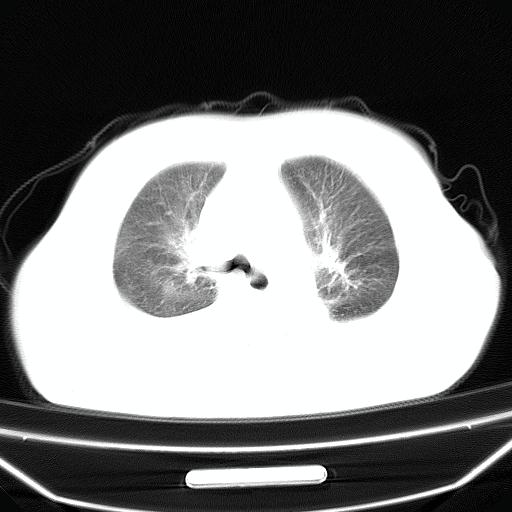

以下是引用jiangjing在2008-4-20 10:43:00的发言:[br]结合病史支持 冠心病[冠状动脉钙化],心功能不全,肺淤血、肺水肿,双侧胸腔与斜裂积液

以下是引用liuyue在2008-4-19 22:25:00的发言:[br]先考虑:1.心衰伴肺水肿、双侧胸腔积液、叶间积液、双下肺不完全性肺不张; [br] 2.冠状动脉粥样硬化。

以下是引用lijuanln在2008-4-19 23:05:00的发言:[br]两侧胸腔积液,肺水肿[br]心包积液[br]提示心衰